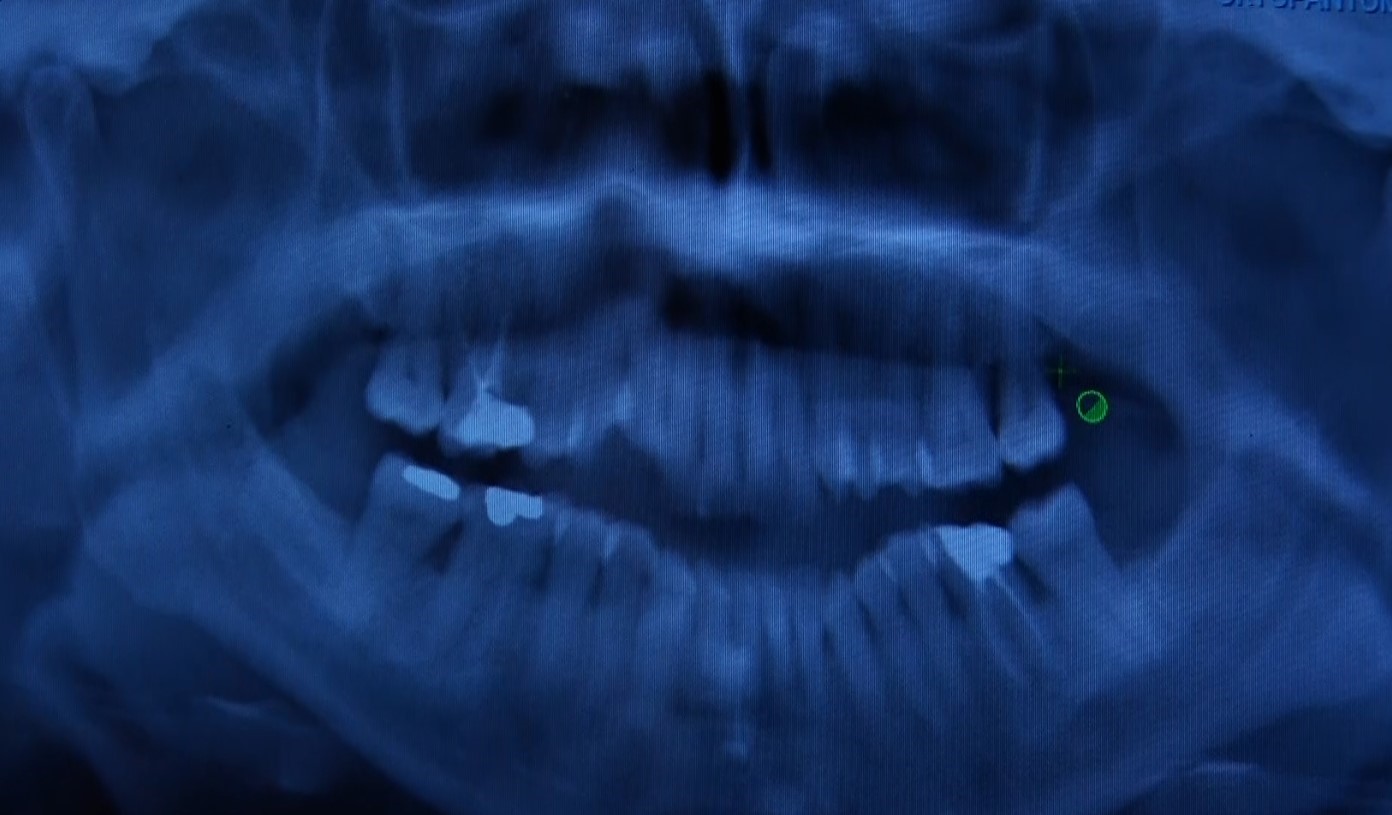

Sarıyer Ağız ve Diş Sağlığı Merkezi Periodontoloji Bölümü’nden Dt. Ebru Özkan Bütün, "Sadece estetik için diş hekimine başvuran hastalarımız oluyor ama sağlık ağızda başlar. Diş eti rahatsızlıkları genelde sessiz ilerler" dedi. Diş eti kanamalarının çoğu zaman ihmal edildiğini belirten Bütün, bu durumun bazı sistemik hastalıkların göstergesi olabileceğini ifade etti.

Bütün, "Hastalar genellikle diş etlerinde kanama, sallanma veya çekilme olduğu zaman bize başvuruyor. Bu şikayetler genellikle hastalığın ileri aşamalarını gösteriyor. Rutin kontroller, erken teşhis ve tedavi için çok önemli" dedi. Tedavinin basit diş taşı temizliğinden cerrahi müdahaleye kadar değişebileceğini belirten